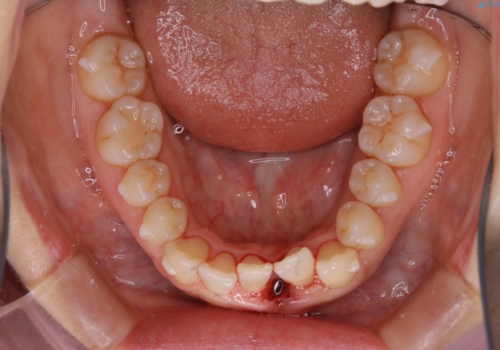

前歯のがたつきを無くすためには、スペースを確保する必要があります。上の前歯のがたつきは軽度ながたつきのため、歯と歯の間を研磨をして、そのスペースを使い並べていきます。下の前歯は、1本前歯を抜いて研磨せずに、その抜歯したスペースを使い並べることになりました。

下の前歯は、スリーインサイザー仕上げと言って、通常前歯は4本ありますが(犬歯はいれていない)、そのどれか1本を抜歯して前歯を3本にして矯正治療を行うことを言います。また、先天的に歯の本数が少ない方もいますので、矯正治療を行っていなくても元々スリーインサイザーの方もいます。